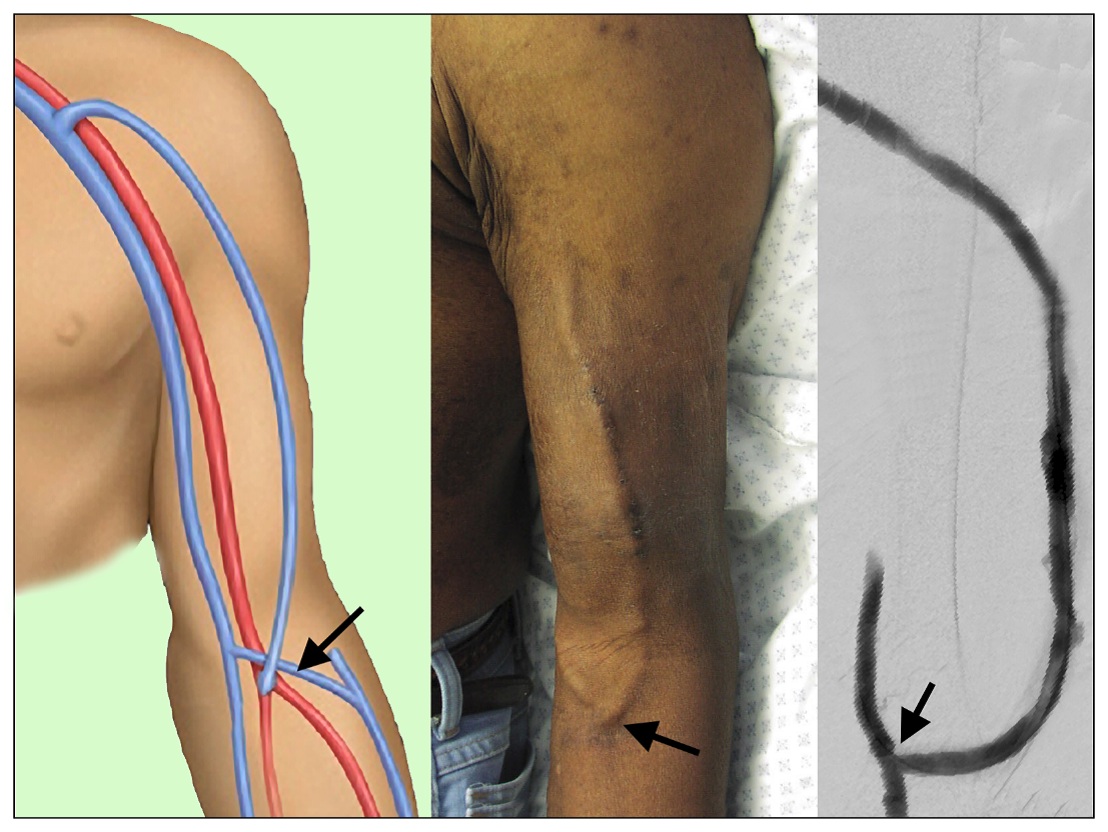

Figure 2

Images of a brachial-cephalic AVF drawing of surgical anatomy (left panel), a matured ready and used for dialysis cannulation (middle panel), and the contrast angiographic appearance (right panel)

Images of a brachial-cephalic AVF drawing of surgical anatomy (left panel), a matured ready and used for dialysis cannulation (middle panel), and the contrast angiographic appearance (right panel)